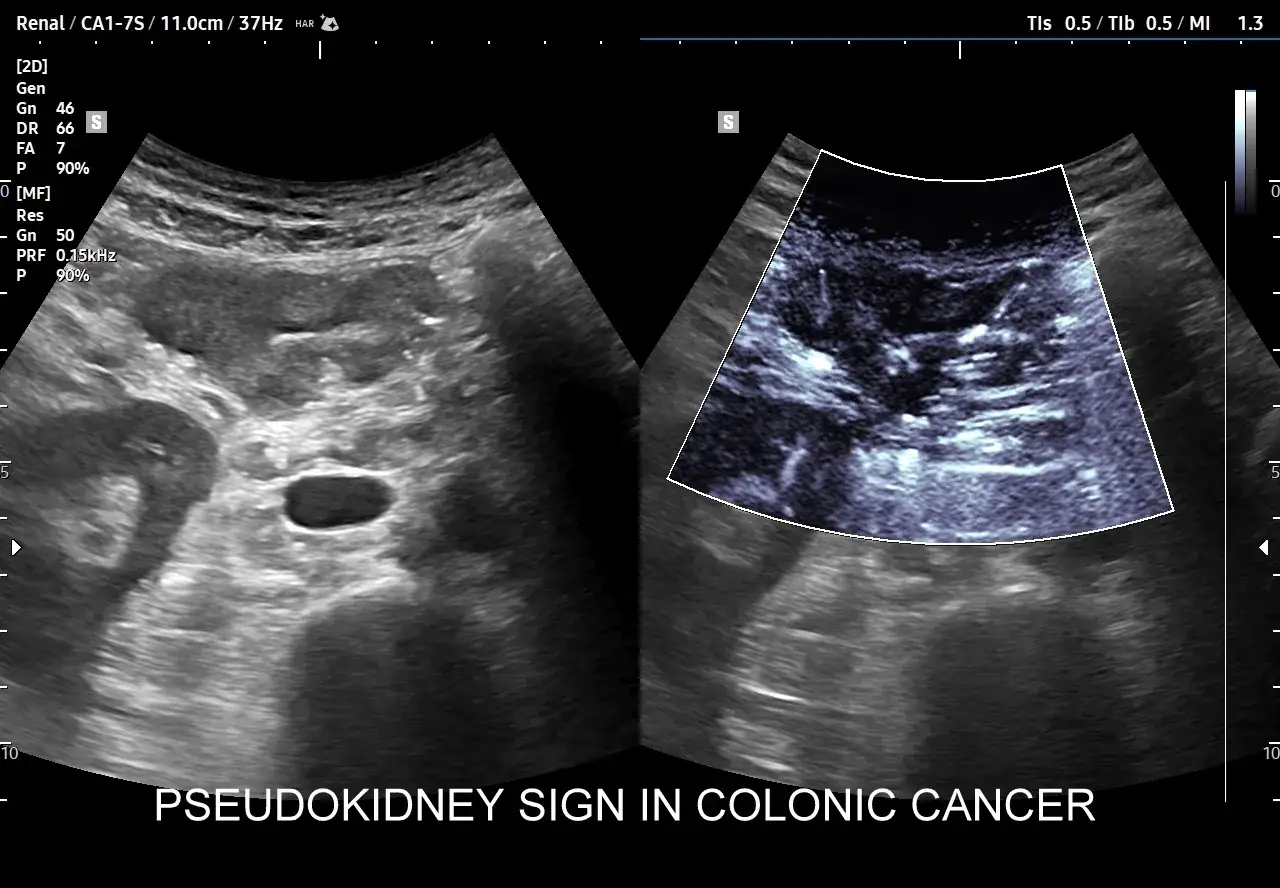

W praktyce oznacza to, że USG może wykryć jedynie duże guzy, które są już w zaawansowanym stadium raka. Dlatego dla skutecznej diagnozy i wczesnego wykrywania raka jelita grubego zaleca się korzystanie z innych metod, takich jak kolonoskopia, która oferuje lepszą czułość i dokładność w wykrywaniu zmian nowotworowych.

Jednym z głównych ograniczeń USG jest jego niska czułość w wykrywaniu wczesnych stadiów raka jelita grubego. Badanie to polega na wykorzystaniu fal dźwiękowych do tworzenia obrazów, co nie zawsze pozwala na uchwycenie małych zmian nowotworowych. W efekcie, pacjenci mogą być narażeni na późniejsze diagnozy, co ogranicza ich szanse na skuteczne leczenie.

Choć kolonoskopia jest główną metodą diagnostyczną, istnieją sytuacje, w których USG może być rozważane. Na przykład, USG może być użyteczne w ocenie pacjentów z objawami raka jelita grubego, takimi jak ból brzucha czy krwawienie. W takich przypadkach, USG może pomóc w szybkiej ocenie stanu pacjenta.Jednakże, należy pamiętać, że USG nie zastąpi kolonoskopia w diagnostyce raka. Warto skonsultować się z lekarzem, aby ustalić, które badania są najbardziej odpowiednie w danym przypadku.